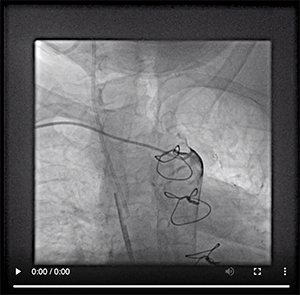

Because the aortic arch was mildly calcified and only mildly tortuous, we were able to negotiate the left subclavian artery with relative ease using a 0.035-inch angled Glidewire Advantage guidewire (Figure 1). Because the patient developed spasm, we chose not to exchange to another catheter and used the JR 4 catheter for the native right coronary artery (Figure 2) and all the grafts, including the LIMA. There was clear diffuse disease progression in the native LAD artery. We discussed intensifying medical therapy and more aggressive dialysis to stabilize her LV function, but we decided against it due to changes in the electrocardiogram and spasm. Video 1 and Video 2 reveal the anatomy defined during catheterization. Video 3, Video 4, and Video 5 illustrate how we negotiated the left subclavian artery and the subselective LIMA angiogram.